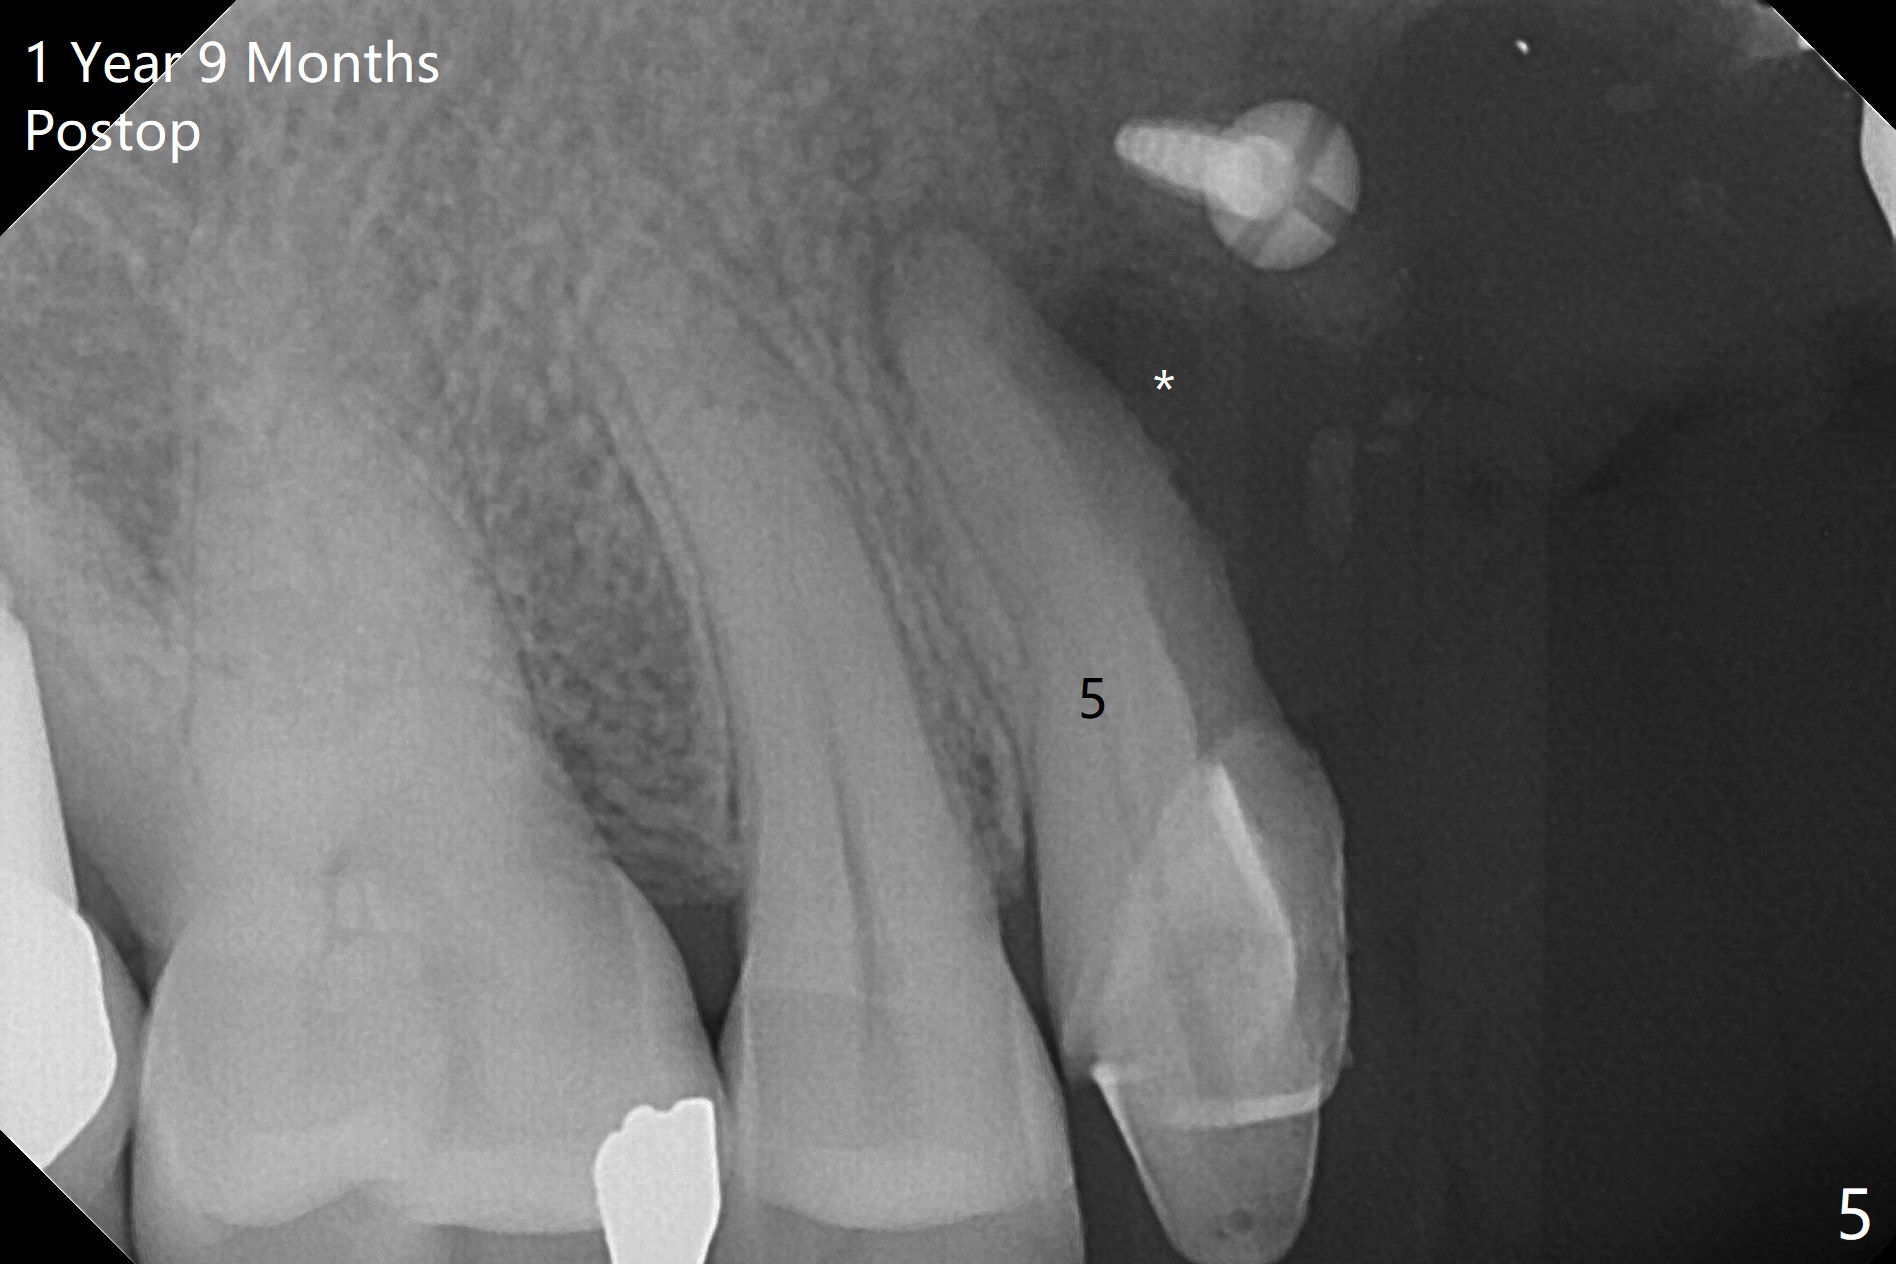

Four months post bone graft with tenting screws at #6 and 7 and implant re-placement at #8, the ridge at #6 and 7 appears to widen slightly, appropriate for narrow implants (Fig.1,2). Guide will be fabricated. The implant at #8 seems to have osteointegrated (Fig.3) with distal gingival recession (Fig.4). One year 5 months later, the tooth #5 is infected with apparently mesial bone loss (Fig.5 *) and papillary erythema and edema (Fig.6). However the pockets are not deep. A gingival embrasure is created between #5 and 6 for self cleansing. The latter does not work. Implants will be placed at #5 and 7 (Fig.7,8).